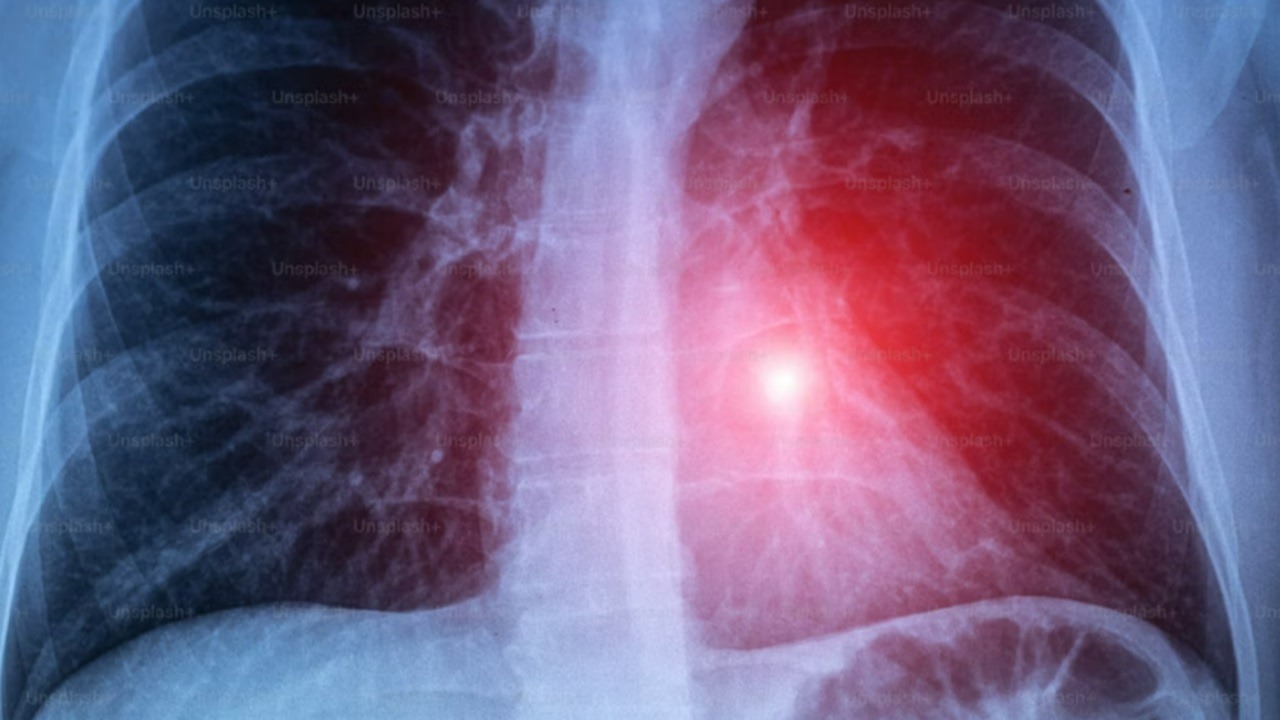

La tuberculosis es una enfermedad infecciosa provocada por una bacteria que se transmite por el aire. El contagio ocurre cuando una persona enferma expulsa partículas al hablar o toser, y otra las inhala, especialmente en espacios cerrados o de convivencia cercana. Aunque puede afectar distintos órganos, el pulmón es el más vulnerable.

Detectarla a tiempo puede ser complicado, ya que suele confundirse con infecciones respiratorias comunes. Uno de los principales signos de alerta es una tos persistente de más de dos semanas, por lo que se recomienda acudir al médico y evitar automedicarse, ya que algunos tratamientos pueden empeorar la enfermedad.